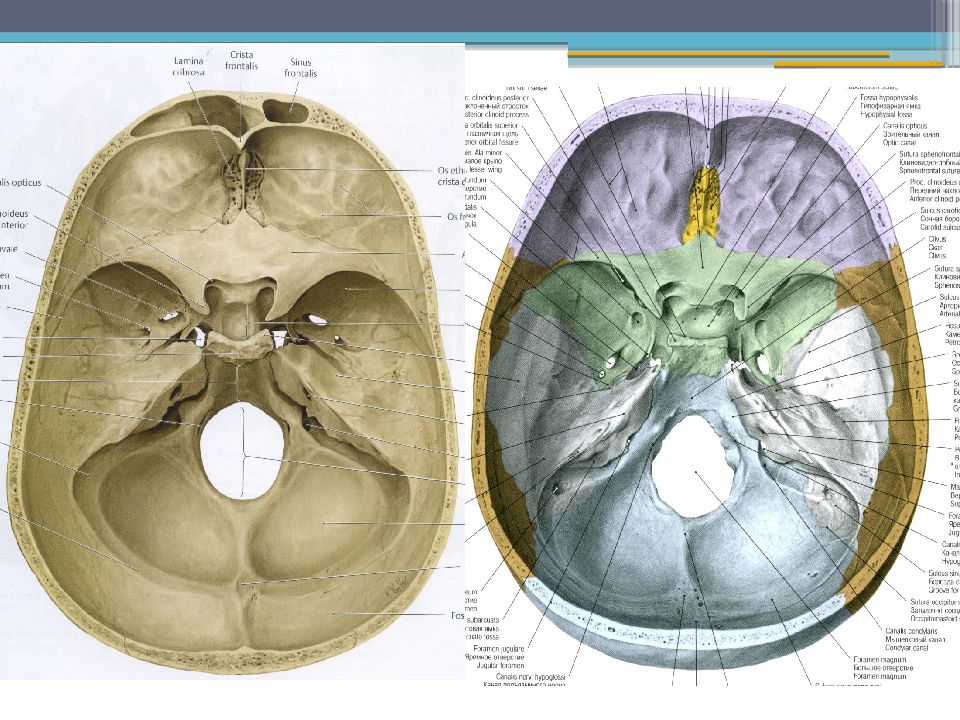

Анатомические детали: Фотографии топографии черепа с нижнего вида

Раздел: Альбом идей